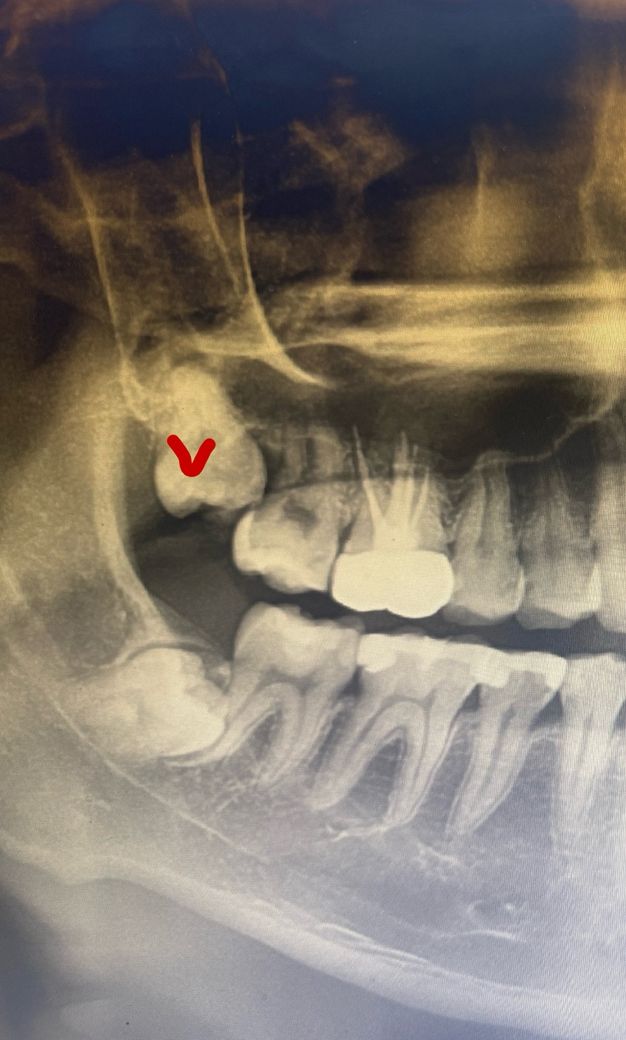

사랑니 발치 질문입니다. 발치가 까다로운 사랑니일까요?

안녕하세요. 우측 상악 사랑니 뽑아야 한다는데 많이 위험할까요? 혓바닥으로 만져지는거 봐선 막 어렵진 않을거같은데

누군 구멍 뚫린다고 대학병원 가보라하거든요.

전 그냥 사랑니 발치 전문뱡원 가려고 하는데 불안해서 질문드립니다ㅜㅜ

1. 맹출한 방향이나 인접 어금니와의 위치관계에 따라 다를 수 있고, 상악동과의 근접여부에 따라서 난이도나 위험성이 나뉩니다.

오른쪽 윗 사랑니가 경사져 있어 어금니 뒤쪽과 걸려 있습니다. 이정도는 굳이 대학병원 안가도 됩니다. 사랑니 전문병원이나 구강외과 전문의가 진료하는 치과 가면 됩니다.